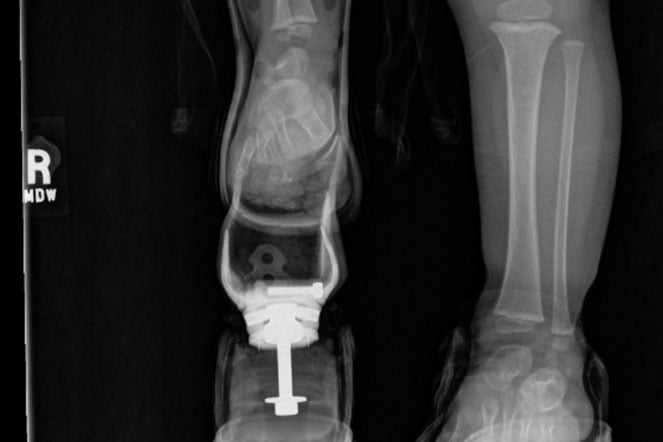

Jokubas X-ray

Jokubas' X-rays